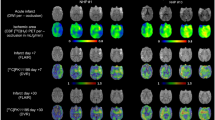

Transient MCA occlusion evokes extensive cerebral ischemic injury with persistent neuroinflammation over 21d

Occlusion of the left MCA for 30 min followed by reperfusion generated a prominent stroke in the left hemisphere of the murine brain. Upon recovery, animals exhibited transient behavioral abnormalities consistent with stroke including unidirectional circling and impaired righting reflex. T2-weighted MRI 2d after injury revealed a hyperintense signal of variable size in the injured ipsilateral hemisphere (Fig. 1A). The absolute stroke size differed among individuals, with a median extent of 44.7mm3 (range: 5.1–139.6mm3) (Suppl. Figure 1A). To assess stroke-induced neuroinflammation, we performed serial PET imaging with 18F-GE180 and evaluated TSPO upregulation in the MRI-defined stroke territory. Averaged brain images demonstrated elevated TSPO signal emanating from the ipsilateral hemisphere (Fig. 1B) over the time course of 21d. At 24 h after surgery, no difference in signal was detected between the ipsilateral and contralateral hemispheres (2.3 ± 0.4 vs 2.6 ± 0.4% injected dose (ID)/g, p = 0.084), nor between MCAo and sham-operated mice (2.3 ± 0.4 vs 2.0 ± 0.3%ID/g, p = 0.388, Fig. 1C). Conversely at 7 days, the TSPO signal was elevated by 52% in the injured ipsilateral hemisphere compared to the contralateral (3.8 ± 0.8 vs 2.5 ± 0.3%ID/g, p < 0.001, Fig. 1D), and by 47% compared to sham (3.8 ± 0.8 vs 2.6 ± 0.7, p < 0.001). This difference declined by 21 days (Suppl Fig. 1B), but remained 30% higher in the ipsilateral compared to contralateral hemisphere after MCAo (3.2 ± 1.2 vs 2.6 ± 0.4%ID/g, p = 0.031, Fig. 1E).

Serial multimodality imaging of infarct region and inflammation after middle cerebral artery occlusion (MCAo). A Representative T2-weighted MRI images identify stroke core and penumbra at 1 and 3 weeks after surgery. B Serial averaged PET images of translocator protein (TSPO) display localized neuroinflammation in the operated ipsilateral hemisphere (left) beginning from 7 days after MCAo. Semi-quantitative analysis calculates the average % injected dose (ID)/g in the highest 10% of voxels in the ipsilateral (ipsi) or contralateral (contra) hemisphere at C 24 h, D 7 days and E 3 weeks after MCAo or sham surgery (sham 24 h n = 5, 7 days n = 8, 3week n = 5; MCAo 24 h n = 23, 7 days n = 26,3week n = 17); one-way ANOVA, Sidak post hoc test

Topical application of ET-1 to brain cortex after craniotomy generates less severe ischemic injury

To obtain a regional stroke of smaller size, we performed a localized craniotomy and topical application of the vasoconstrictor ET-1 to the right hemisphere brain parenchyma. On recovery, animals exhibited minor behavioral signs of stroke, but tended to recover faster than from MCAo surgery without prolonged behavioral changes. T2-weighted MRI did not identify signal hyperintensity at the site of craniotomy and ET-1 application (Fig. 2A), reminiscent of transient ischemia rather than overt stroke. Serial PET imaging with 18F-GE180 revealed gradually increasing TSPO signal from the injured right hemisphere cerebral cortex at the location of craniotomy, but did not distinguish between vehicle and ET-1 application (Fig. 2B). At 24 h, ipsilateral and contralateral hemispheres showed similar basal levels of TSPO signal and no difference was observed at the site of ET-1 or vehicle application (2.3 ± 0.5 vs 2.4 ± 0.3%ID/g, p = 0.824, Fig. 2C). By 7 days after surgery ET-1 animals exhibited an 80% increase in TSPO signal at the site of craniotomy compared to the contralateral side (4.2 ± 1.0 vs 2.3 ± 0.7%ID/g, p < 0.001, Fig. 2D), but this elevation was similar in vehicle-treated mice (4.2 ± 1.0 vs 3.7 ± 1.1%ID/g, p = 0.773). This unilateral elevation in TSPO signal in ET-1 and vehicle craniotomy animals remained at 21 days (Fig. 2E), with no change in the contralateral hemisphere over time (Suppl Fig. 2). This similar TSPO upregulation between ET-1 and vehicle application suggested an inflammatory response to epithelium from the craniotomy alone.

Serial multimodality imaging of brain morphology and inflammation after craniotomy and topical endothelin-1 (ET-1) application. A Representative T2-weighted MRI images cannot distinguish a stroke core penumbra region at 1 or 3 weeks after surgery. B Serial averaged TPSO PET images display gradually increased neuroinflammation in the operated ipsilateral hemisphere (right) beginning from 7 days and increasing to 21 days after craniotomy. Semi-quantitative analysis reveals elevated %ID/g in the hottest 10% of voxels in the ipsilateral (ipsi) or contralateral (contra) hemisphere at C 24 h, D 7 days, and E 3 weeks after craniotomy and vehicle or ET-1 application (vehicle 24 h n = 6, 7 days n = 3, 3 week n = 04; ET1 24 h n = 14, 7 days n = 13, 3week n = 10); one-way ANOVA, Sidak post hoc test